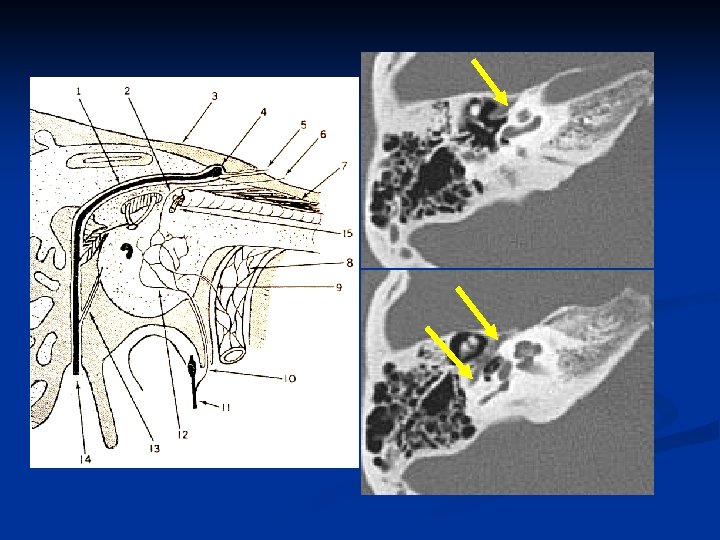

Ear n Keywords: -- Tympanic membrane, -- Ossicular chain (Malleus, Incus, Stapes) -- Facial nerve -- Cochlea, Semicircular canal -- External and internal auditory canals

Orbit n Keywords: -- Extraconal & Intraconal -- Lacrimal glands -- Muscles -- Superior & inferior orbital fissures -- Optic canal

Superior & inferior orbital fissures